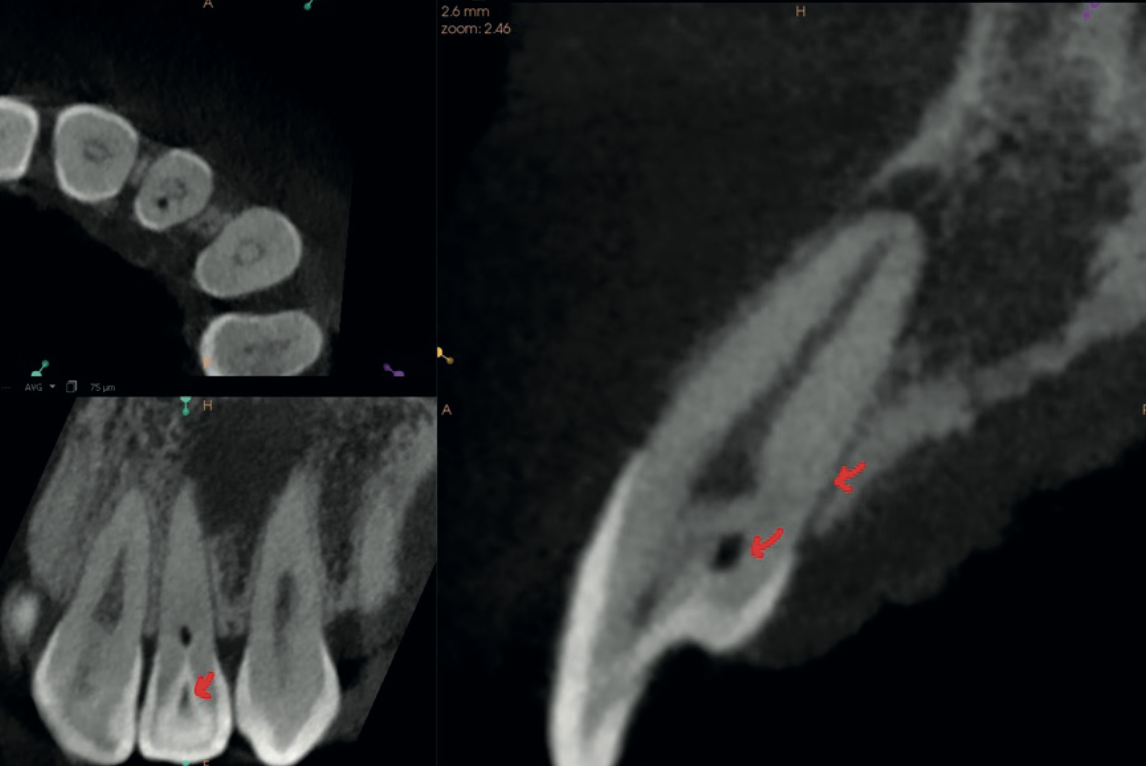

High-resolution CBCT multiplanar view revealing dens invaginatus

General Diagnostic CS 9600

Unexplained Pain, No Caries, No Trauma — CBCT Solved It at 75 Microns

A 29-year-old with anterior pain that defied diagnosis. High-resolution CBCT revealed a rare Type III Dens Invaginatus.